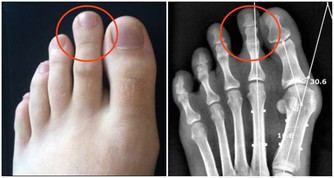

腎臟已經出現損傷,身體會有這幾個表現

1、精神不振、疲勞、乏力,還會出現無緣由的腰酸背痛。

2、胃口不好、噁心嘔吐。

3、晨起眼瞼或顏面水腫,下肢水腫,且按壓後凹陷部位無法馬上恢復。

4、小便有泡沫,久久都不消。

5、尿量變多或變少,都可能是腎臟疾病。